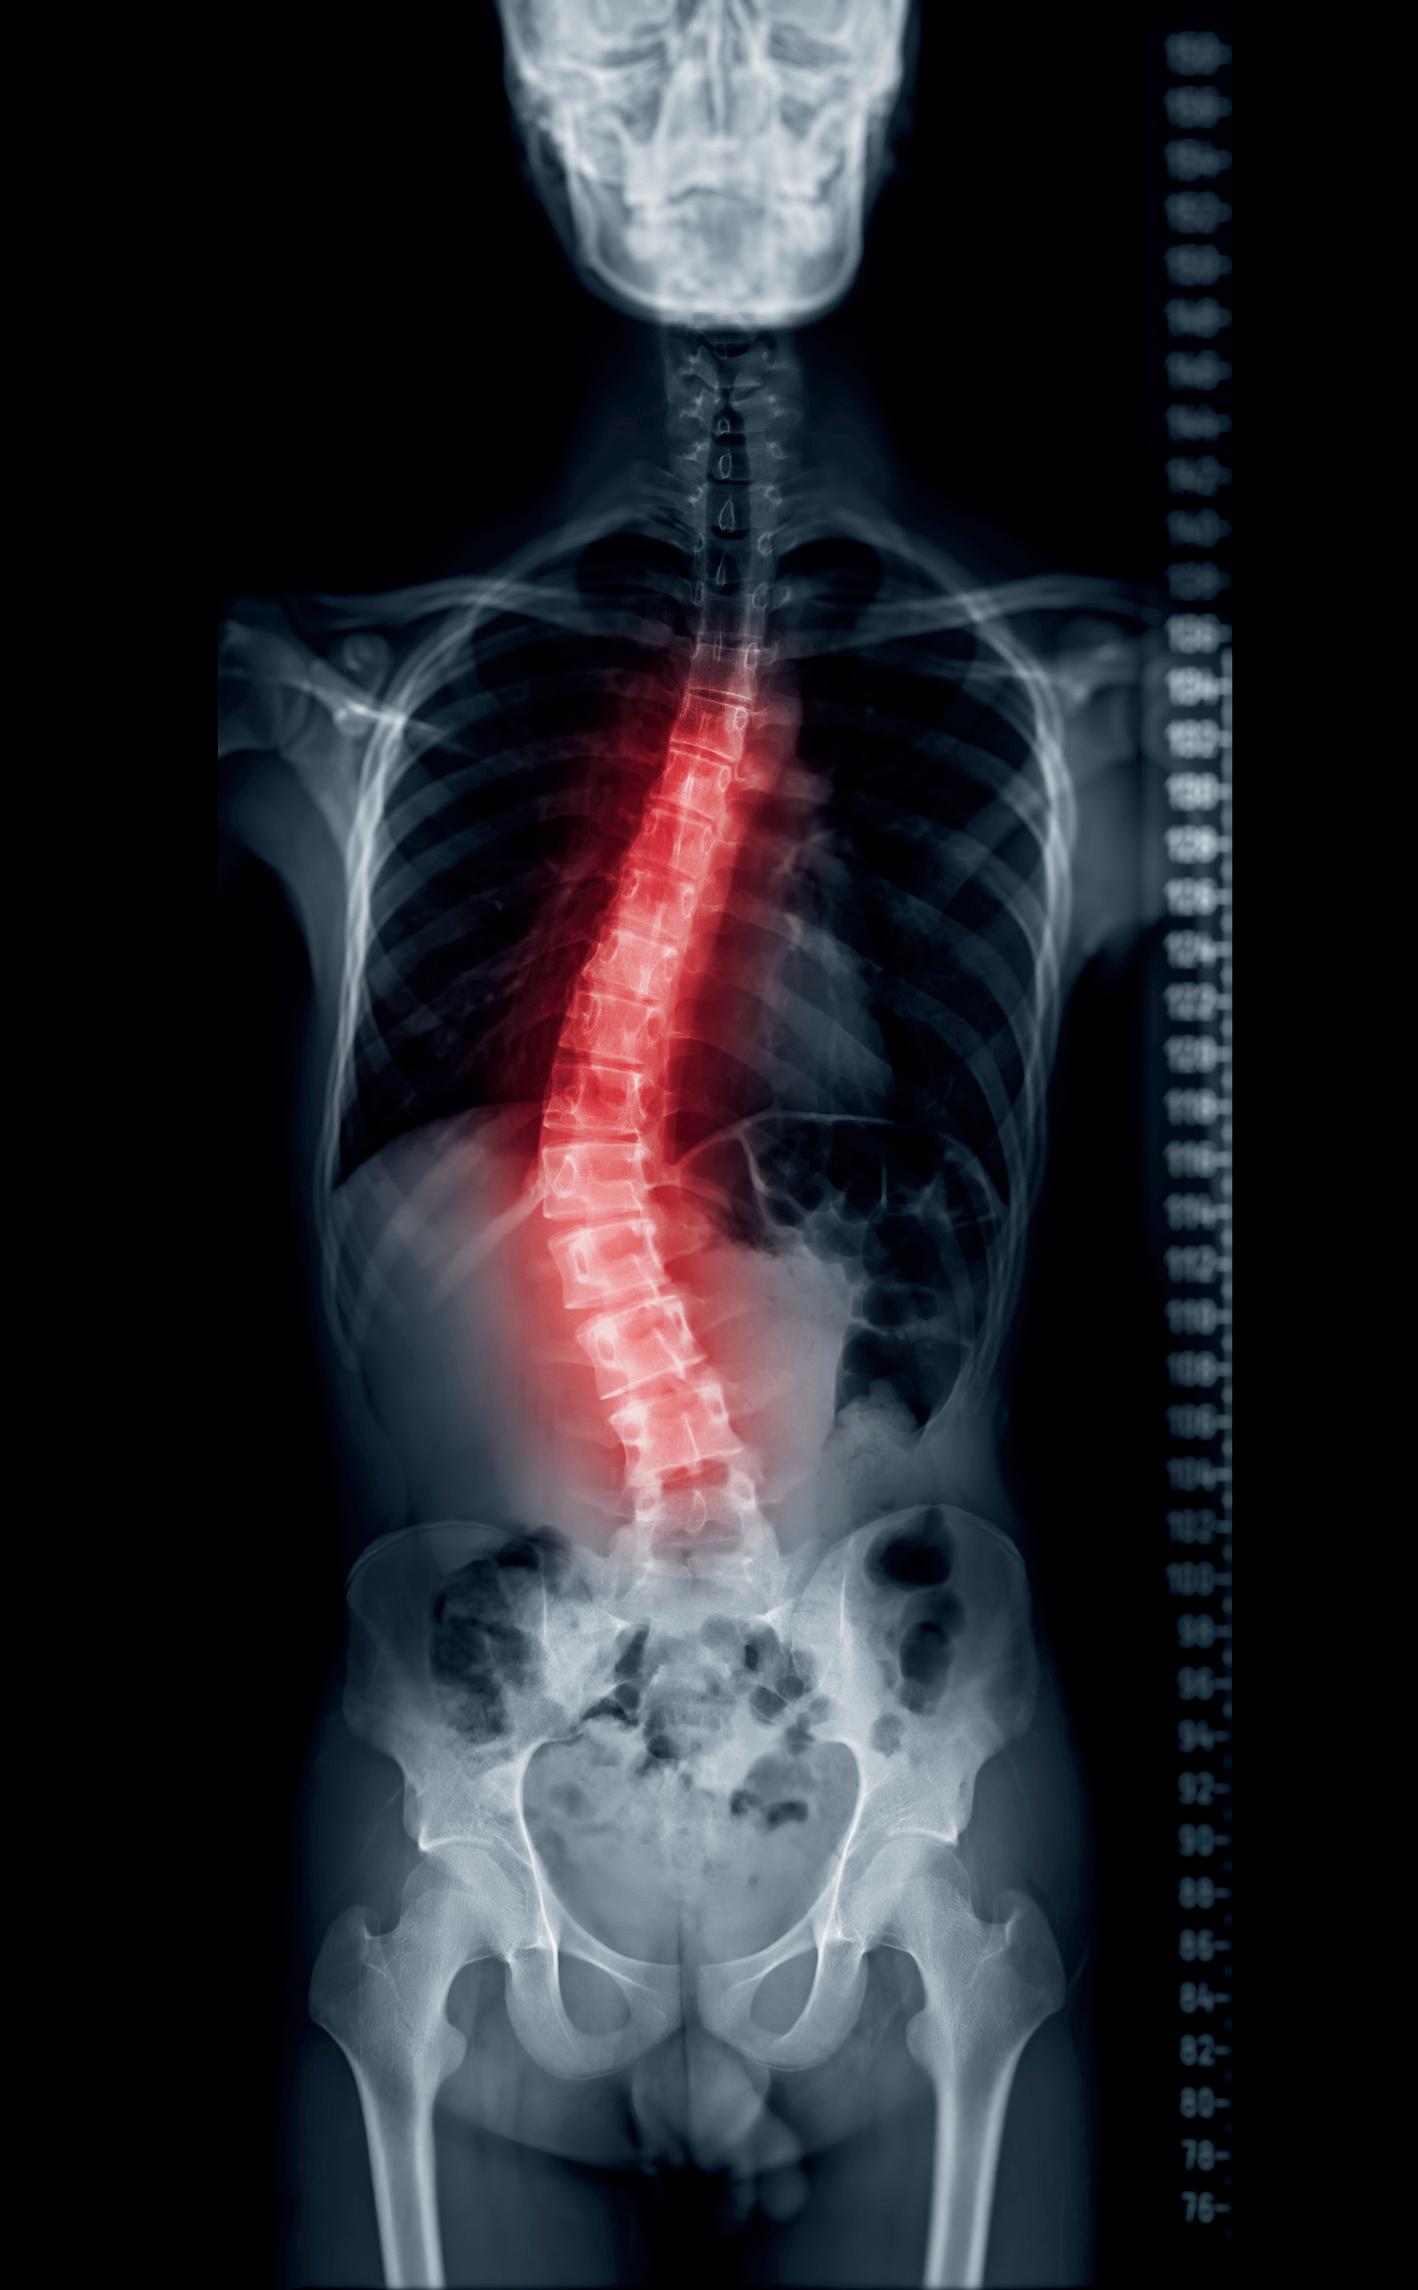

TheEvolutionofConservative ScoliosisTreatment:Advances andClinicalEfficacy.

Ana Claudia dos Santos Rosa, Physiotherapist, researcher, and specialist in non-invasive scoliosis treatment, advancing Global Postural Re-education (GPR) and Schroth Method applications for spinal rehabilitation and musculoskeletal health.

The aging population and workforce sustainability demand a re-evaluation of eldercare models. Our analysis of humanized caregiving challenges the traditional biomedical approach, advocating for personcentered frameworks that prioritize dignity, autonomy,andwell-being. Meanwhile, advancements in conservative scoliosis treatment and ADHD research highlight the increasing interdisciplinarity of medical science. Integrating neuroscience, rehabilitation techniques, and cognitive interventions will lead to more personalized andeffectivetreatmentmodels.